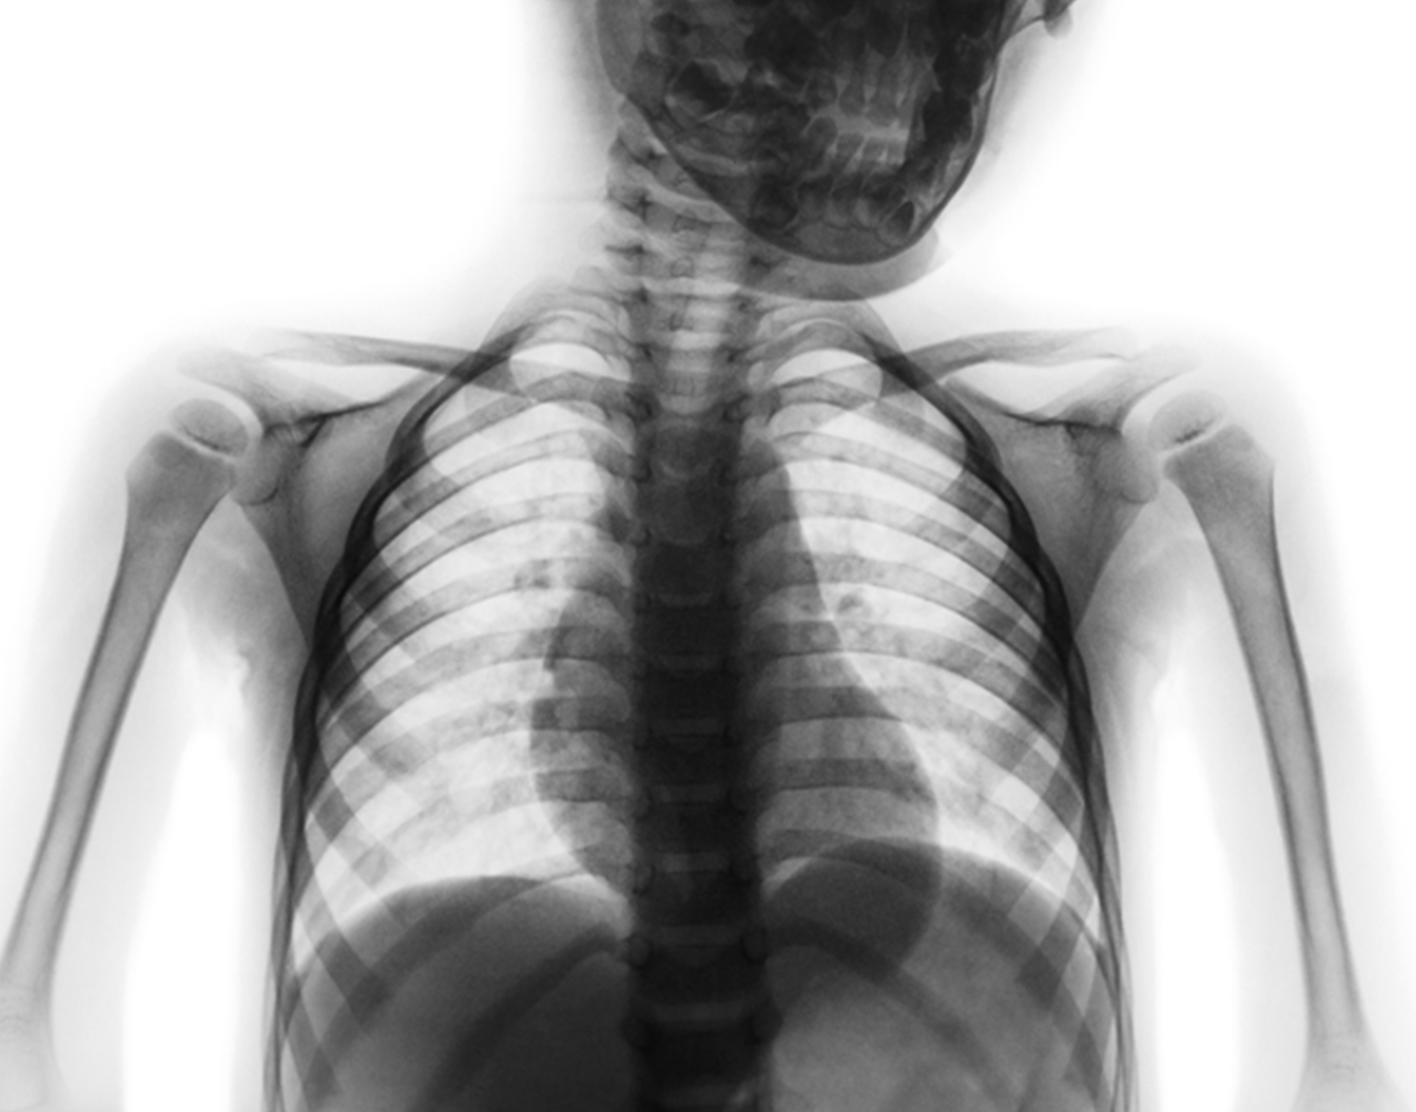

Thoracic spine x-ray

A thoracic spine x-ray is an x-ray of the 12 chest (thoracic) bones (vertebrae) of the spine. The vertebrae are separated by flat pads of cartilage called disks that provide a cushion between the bones.